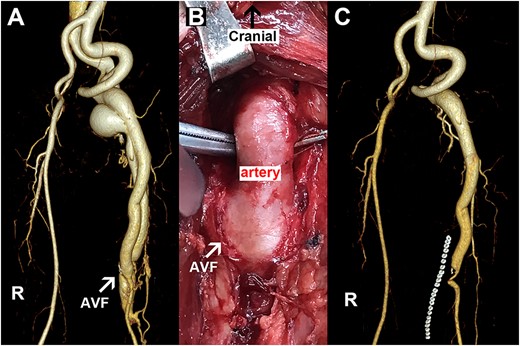

A 53-year-old male patient complained of having had discomfort in his left thigh for 5 months. The physical examination revealed that the patient had edema of the left thigh and local irritation with an abnormal tremor. Forty years earlier, he had been injured by marble on his left thigh. Hospital CT showed soft tissue edema with no femoral or vascular abnormalities, so no attention was taken seriously. The patient’s laboratory tests were unremarkable on admission. Next, the CTA confirmed an abnormal fistula located in the middle of the left femoral artery (Fig. 2A), and the fistula diameter was 12 mm. He was diagnosed with posttraumatic AVF, for which the main treatment modality is surgical excision of the AVF, but there are also newer treatments such as endovascular stenting, embolization, and artificial vascular grafts. In this case, the fistula was a high-flow AVF due to its large size and location in the femoral vessels. Not only was there a risk of multiple endovascular treatments, but the material available for endovascular treatment was not fully adequate for this AVF. We, therefore, recommended him consider the surgical removal rather than endovascular intervention. After assessing the patient’s basic vital signs, we performed the procedure under general anesthesia with an incision in the left medial thigh. As shown in Fig. 2B, the fistula was transected, and the inflow artery and outflow vein were repaired with 6–0 Prolene sutures. Postoperatively, the thrill in the left thigh disappeared immediately. At the end of the procedure, the abnormal tremor in the patient’s inner thighs also disappeared, and the edema in the lower limbs was significantly reduced. On Day 1 post-surgery, the patient was given prophylactic anticoagulant therapy with enoxaparin sodium. Two days later, he was able to walk around without any pain or swelling. Before his discharge, the postoperative CTA scan also confirmed that there were no abnormal postoperative fistulas or venous angiography (Fig. 2C). During the 6-month follow-up, the patient experienced no symptoms or complications.

Representative images for Case 2. (A) Preoperative image with the arrow pointing to an AVF. (B) Intraoperative picture with the arrow indicating an AVF. (C) Postoperative imaging data. R, right side; AVF, arteriovenous fistula.